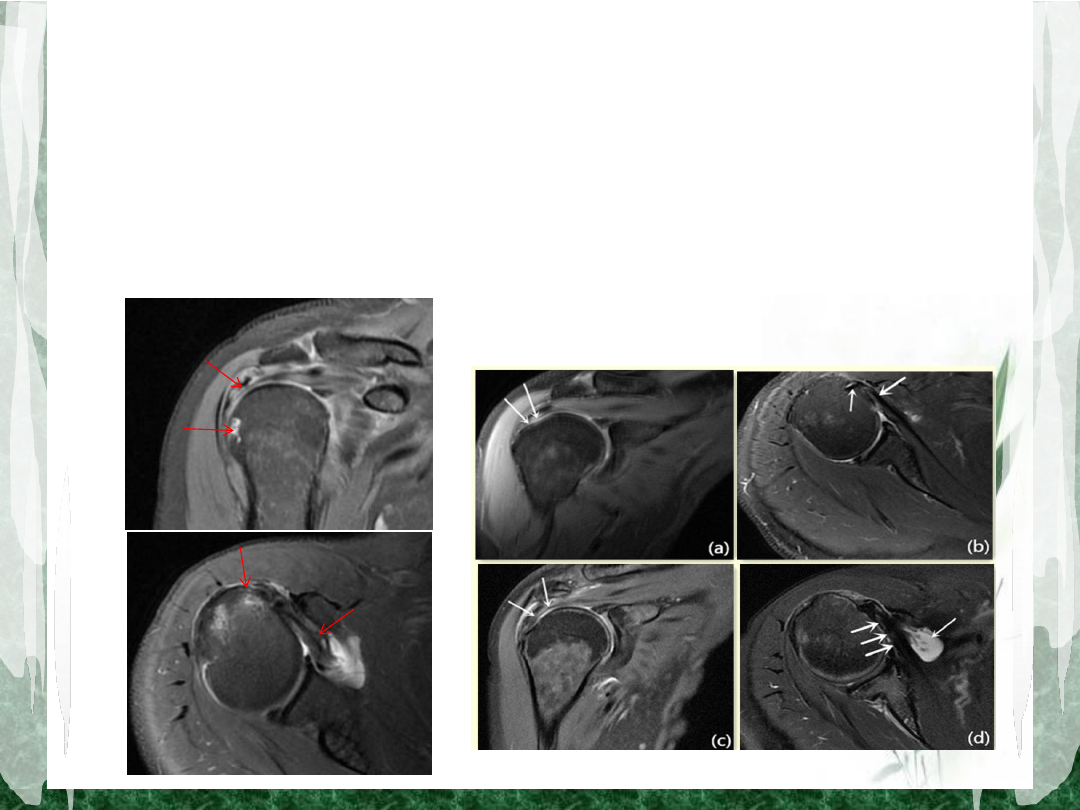

影像学表现

• MRI

在斜冠状位和斜矢状位

T2

抑脂像显示肩袖信

号不同程度增高、边缘毛糙;肌腱局部连续性中

断、断端回缩、肩关节囊与肩峰下滑囊相通等;